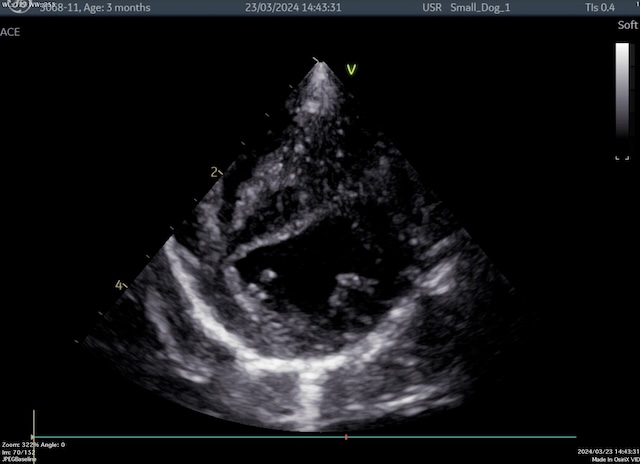

本症例は生後3ヶ月の幼犬でした。

肺動脈の弁性狭窄は先天性心疾患の一つで、狭窄具合が酷ければ酷いほど、右心室に圧力負荷が増え、右心不全や心室性不整脈などの原因になり、突然死を起こすリスクが高くなります。

本症例は狭窄部の血流が下で示すように7m/secを近くあり、圧較差が190mmHg近くありました。

重度の狭窄があるために、心室中隔も左心室側に変位が認められています。

拡大後は流速が3m/sec以下まで落ち、圧較差では150mmHg程度の減圧に成功いたしました。